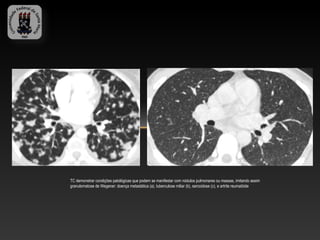

TC demonstrar condições patológicas que podem se manifestar com nódulos pulmonares ou massas, imitando assim

granulomatose de Wegener: doença metastática (a), tuberculose miliar (b), sarcoidose (c), e artrite reumatóide